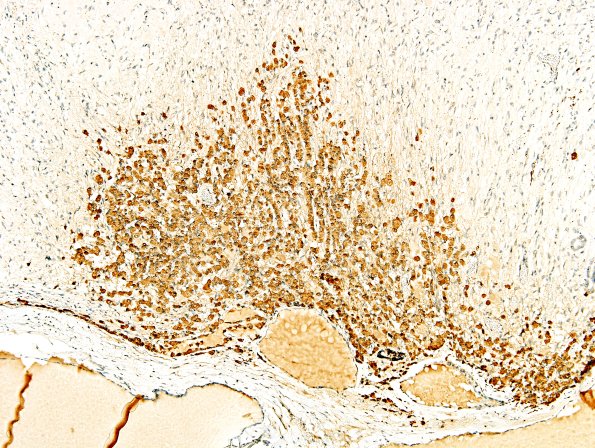

Basophil invasion at 3 magnifications immunostained for ACTH. (ACTH IHC)